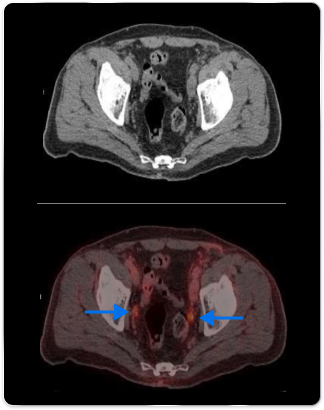

High-risk patient with newly diagnosed prostate cancer

Age

63

PSA (ng/mL)

26

Gleason Score

4 + 3

PYLARIFY may have helped prevent overtreatment